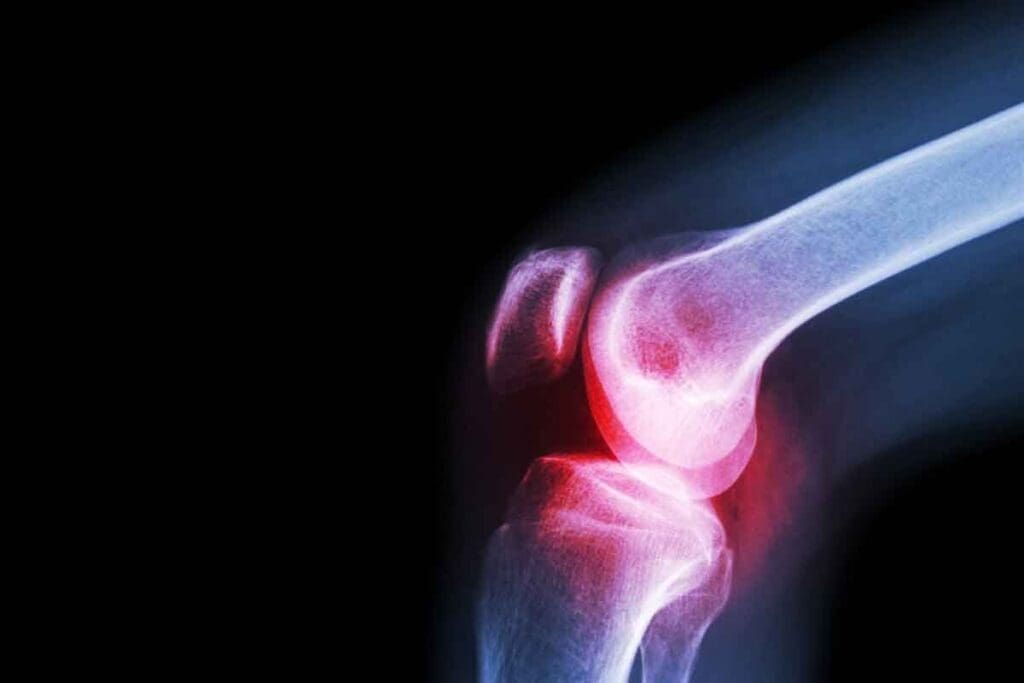

Persistent and Progressive Bone Pain

Persistent and progressive bone pain is a common symptom. This pain can be very severe. It’s often mistaken for sports injuries or growing pains, mainly in kids and teens.

Pathological Fractures

Ewing sarcoma can weaken bones, leading to pathological fractures. These fractures happen without major trauma and can be a symptom.